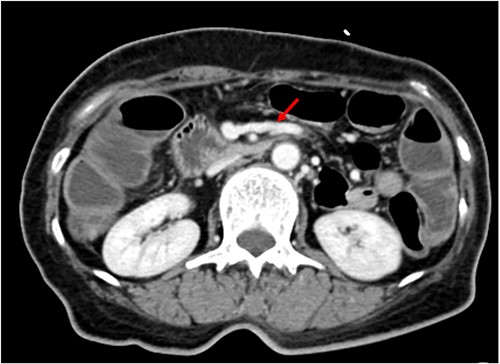

We made an incision avoiding the tumor. The patient’s abdominal cavity showed overall adhesion due to previous surgery. We found tumor invading or being adherent to the duodenum and superior mesenteric vein (Fig. 3). We thought that superior mesentery vein (SMV) collapsed due to compression, but it was identified completely occluded due to invasion. We also found that jejunal first branch was very dilated due to obstruction (Fig. 4). We performed completion right hemicolectomy with duodenal segmental resection, SMV resection and anastomosis (Fig. 5). Anterior resection was performed for the accompanying sigmoid colon cancer.

Dilated jejunal first branch of superior mesenteric vein (red arrow).